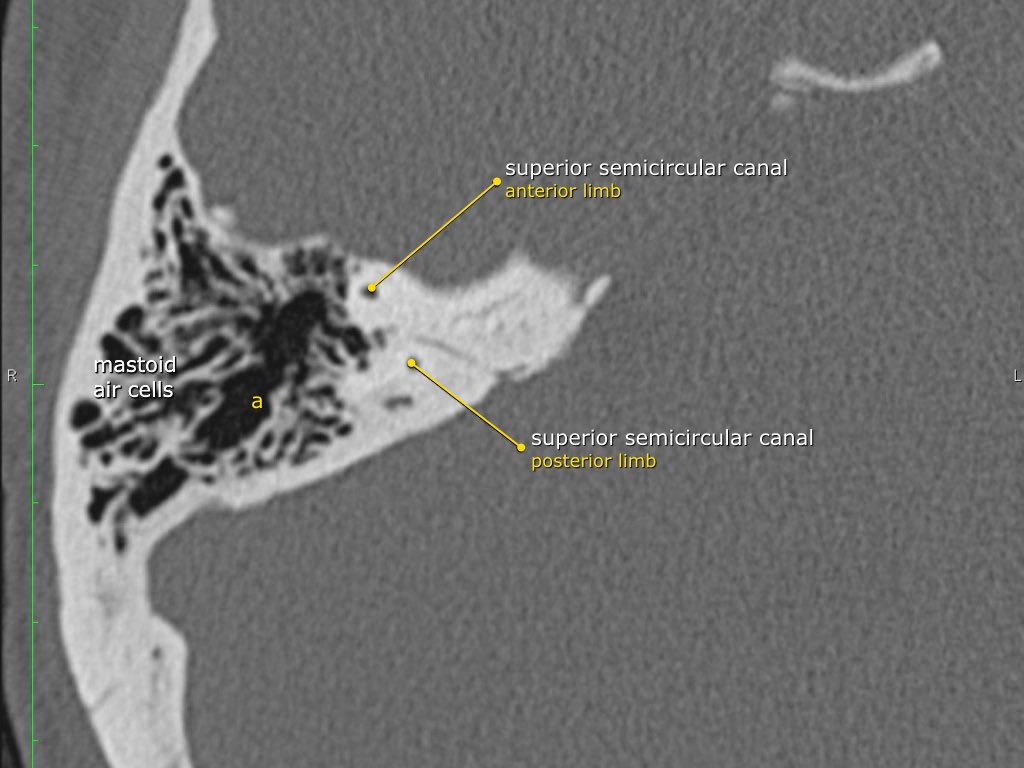

Trong bài tổng quan này, chúng tôi trình bày giải phẫu bình thường trên mặt phẳng cắt ngang (axial) và mặt phẳng cắt đứng ngang (coronal) của xương thái dương thông qua việc duyệt qua các hình ảnh.

Một số cấu trúc được thảo luận chi tiết hơn với trọng tâm là các bệnh lý liên quan.

Giải phẫu xương đá trên mặt phẳng cắt ngang (Axial)

Cuộn qua các hình ảnh.